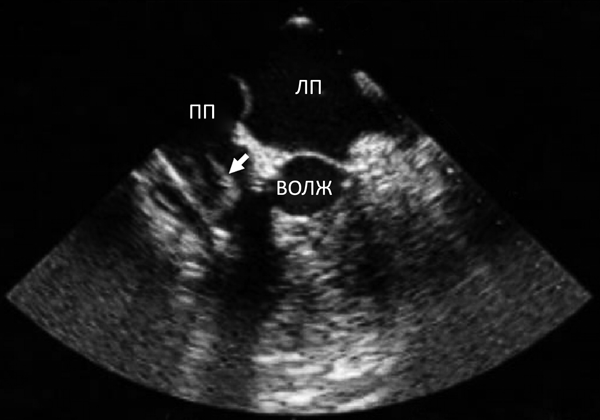

2.1. Эхокардиографические признаки:

• Вегетация,

• Абсцесс, псевдоаневризма, интракардиальная фистула.

• Перфорация или аневризма клапана.

• Новое частичное раскрытие искусственного клапана.

• Трансторакальная эхокардиография.

• Чреспищеводная эхокардиография: подозрение на ИЭ при нормальном трансторакальном исследовании, повторно через 5–7 дней после первого исследования если клинически сильные подозрения на ИЭ.

Второй компонент - это проявление местной инфекции. Микроорганизмы образуют колонии на внутренней оболочке сердца, чаще всего на клапанах - так называемые вегетации. Вегетации могут выявляться при ультразвуковом исследовании сердца. Иногда при обычной эхокардиографии они не видны, и тогда для диагностики необходимо ультразвуковое исследование через пищевод (похожее на гастроскопию, только специальным ультразвуковым датчиком).